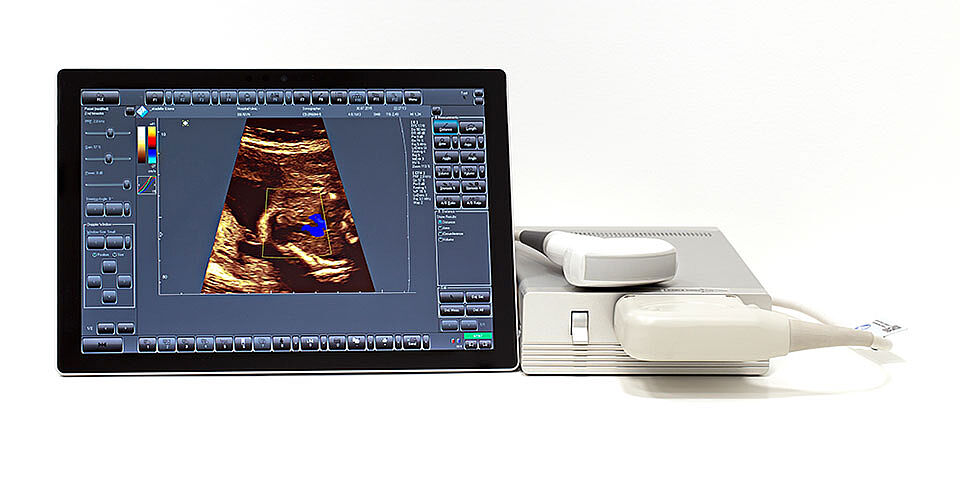

Цифровая ультразвуковая система SmartUs

Ультразвуковой сканер SmartUs - инновационная и чрезвычайно мощная ультразвуковая система на современнейшей платформе для любых УЗ исследований.

Его открытая архитектурная платформа включает последние технологические достижения формирования и обработки ультразвуковых лучей.

Гибкий дизайн

- Большой размер монитора для стационарного использования и чувствительный сенсорный экран (* опция);

- Возможность одновременного использования с любым количеством рабочих станций (ПК, ноутбук или планшет);

- В мобильном использовании - очень легкая система;

- Легкая и быстрая замена датчиков;

SmartUs - оптимальный выбор для медицинского центра и поликлиники.

Доступен с одним SmartUs EXT-1H и тремя SmartUs EXT-3H портами для УЗИ датчиков.